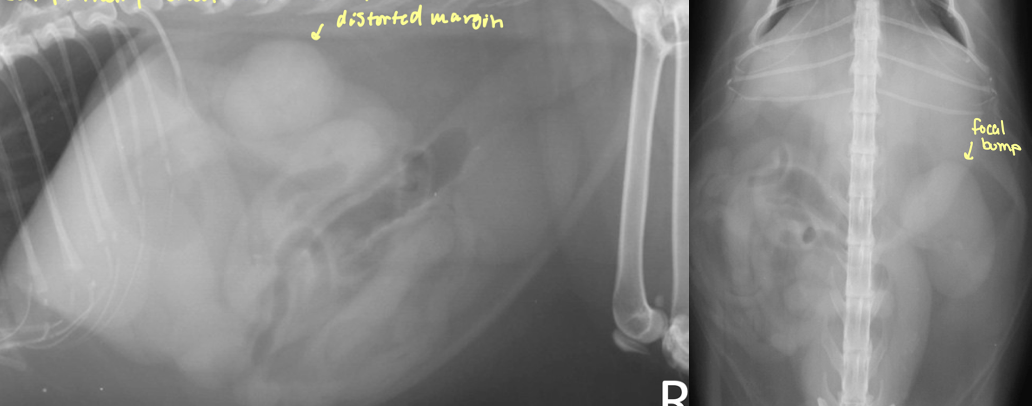

what is going on with this kidney

mass - neoplasia

focal/multifocal nodules with renal enlargement

mass - cystic carcinoma

hypo/iso/hyperechoic ill defined mass ± cysts and mineralization